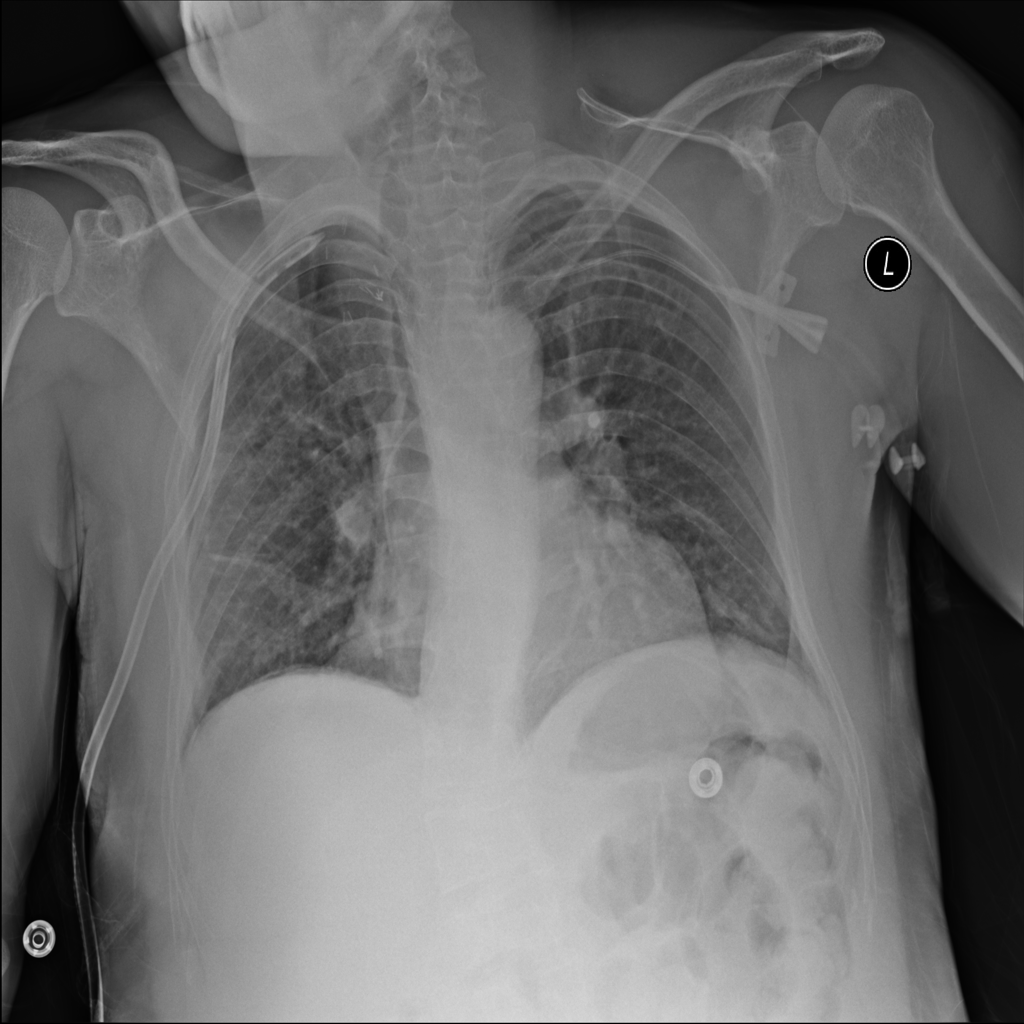

PAT-DB80 · IMG-001Atelectasis

PAT-DB80 · IMG-001

PA